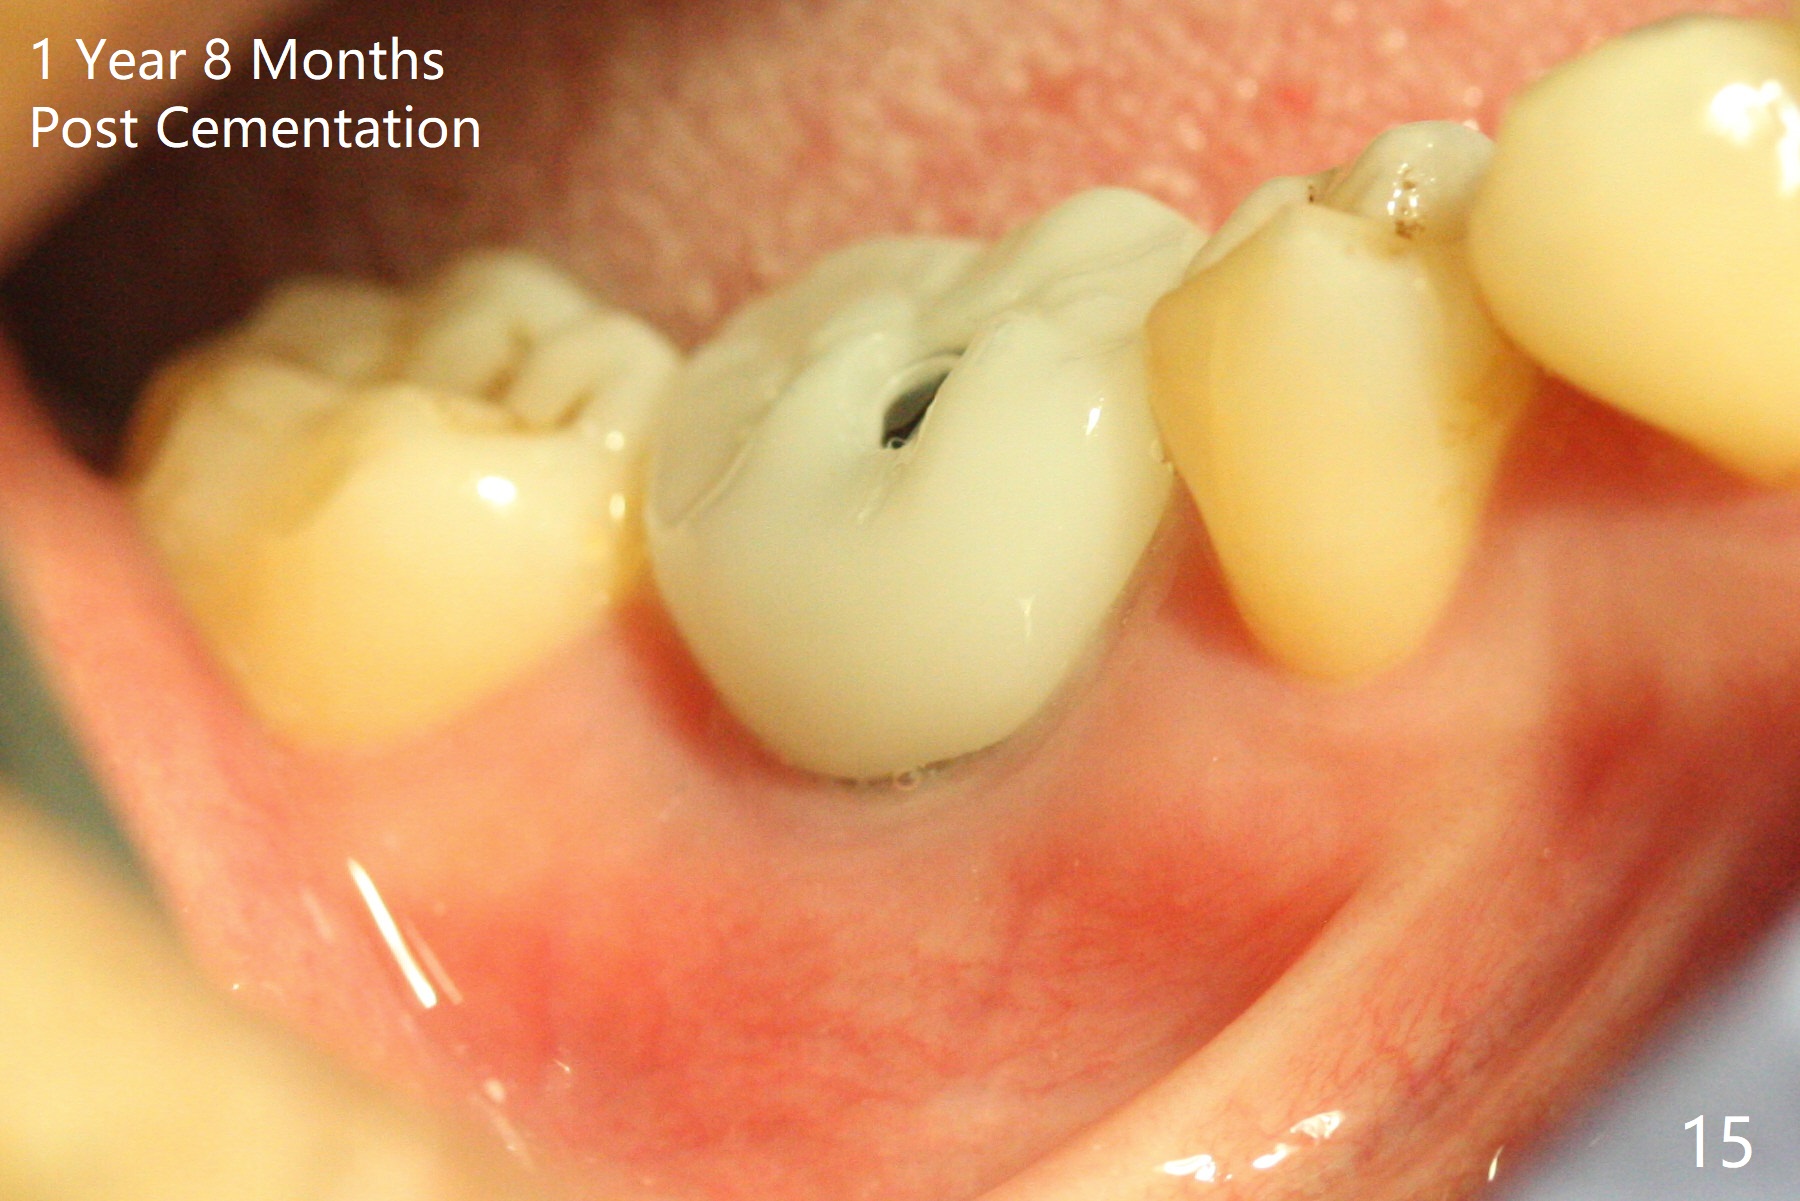

Fortunately no paresthesia is reported postop. Why is the Inferior Alveolar Canal not violated? Fig.7 is a coronal section of CBCT taken for a 40-year-old man at the lower 1st molar (at the septum). At the region, the Canal (brown circle) is close to the lingual plate (L). Because of severe bone loss of the lingual plate of this case (Fig.8 *), osteotomy is intentionally created buccal (green). The deep osteotomy may not contact the Canal, while the hemorrhage may stem from the medullary space (M in Fig.4,7). Bone morphology at the coronal end of the implant apparently changes 4 months postop, suggesting osteointegration (Fig.9). Impression is taken. Bone density around the implant at the crest seems to increase (Fig.10), while there is no soft tissue deficiency 10 months post cementation (Fig.11). The bone appears to regenerate toward the abutment, particularly distally, 14.5 months post cementation (Fig.12). Periimplantitis develops (bleeding on water pik and erythematous and tender buccal gingiva) 1 year 7 months post cementation (Fig.13,14). The 1st three threads are exposed (*). Bone graft with PRF and 6-month membrane or Cytoplast will be needed. Pain disappears 3 days of oral antibiotic. The gingiva looks healthy 1 month later when he returns for bone graft (Fig.15). But the lingual gingival cuff is not so healthy when the crown/abutment is removed (Fig.16 <). Bone graft is not done. For those patients with suboptimal oral hygiene, implants should be placed as low as possible, better with guide for precision.